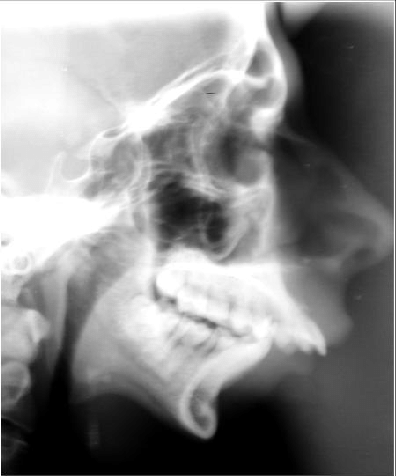

2. Lateral Cephalogram:

Periodic radiographs taken can help to estimate growth of the jaw.